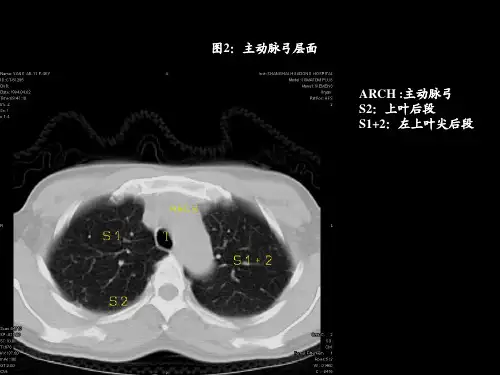

胸部常见病变